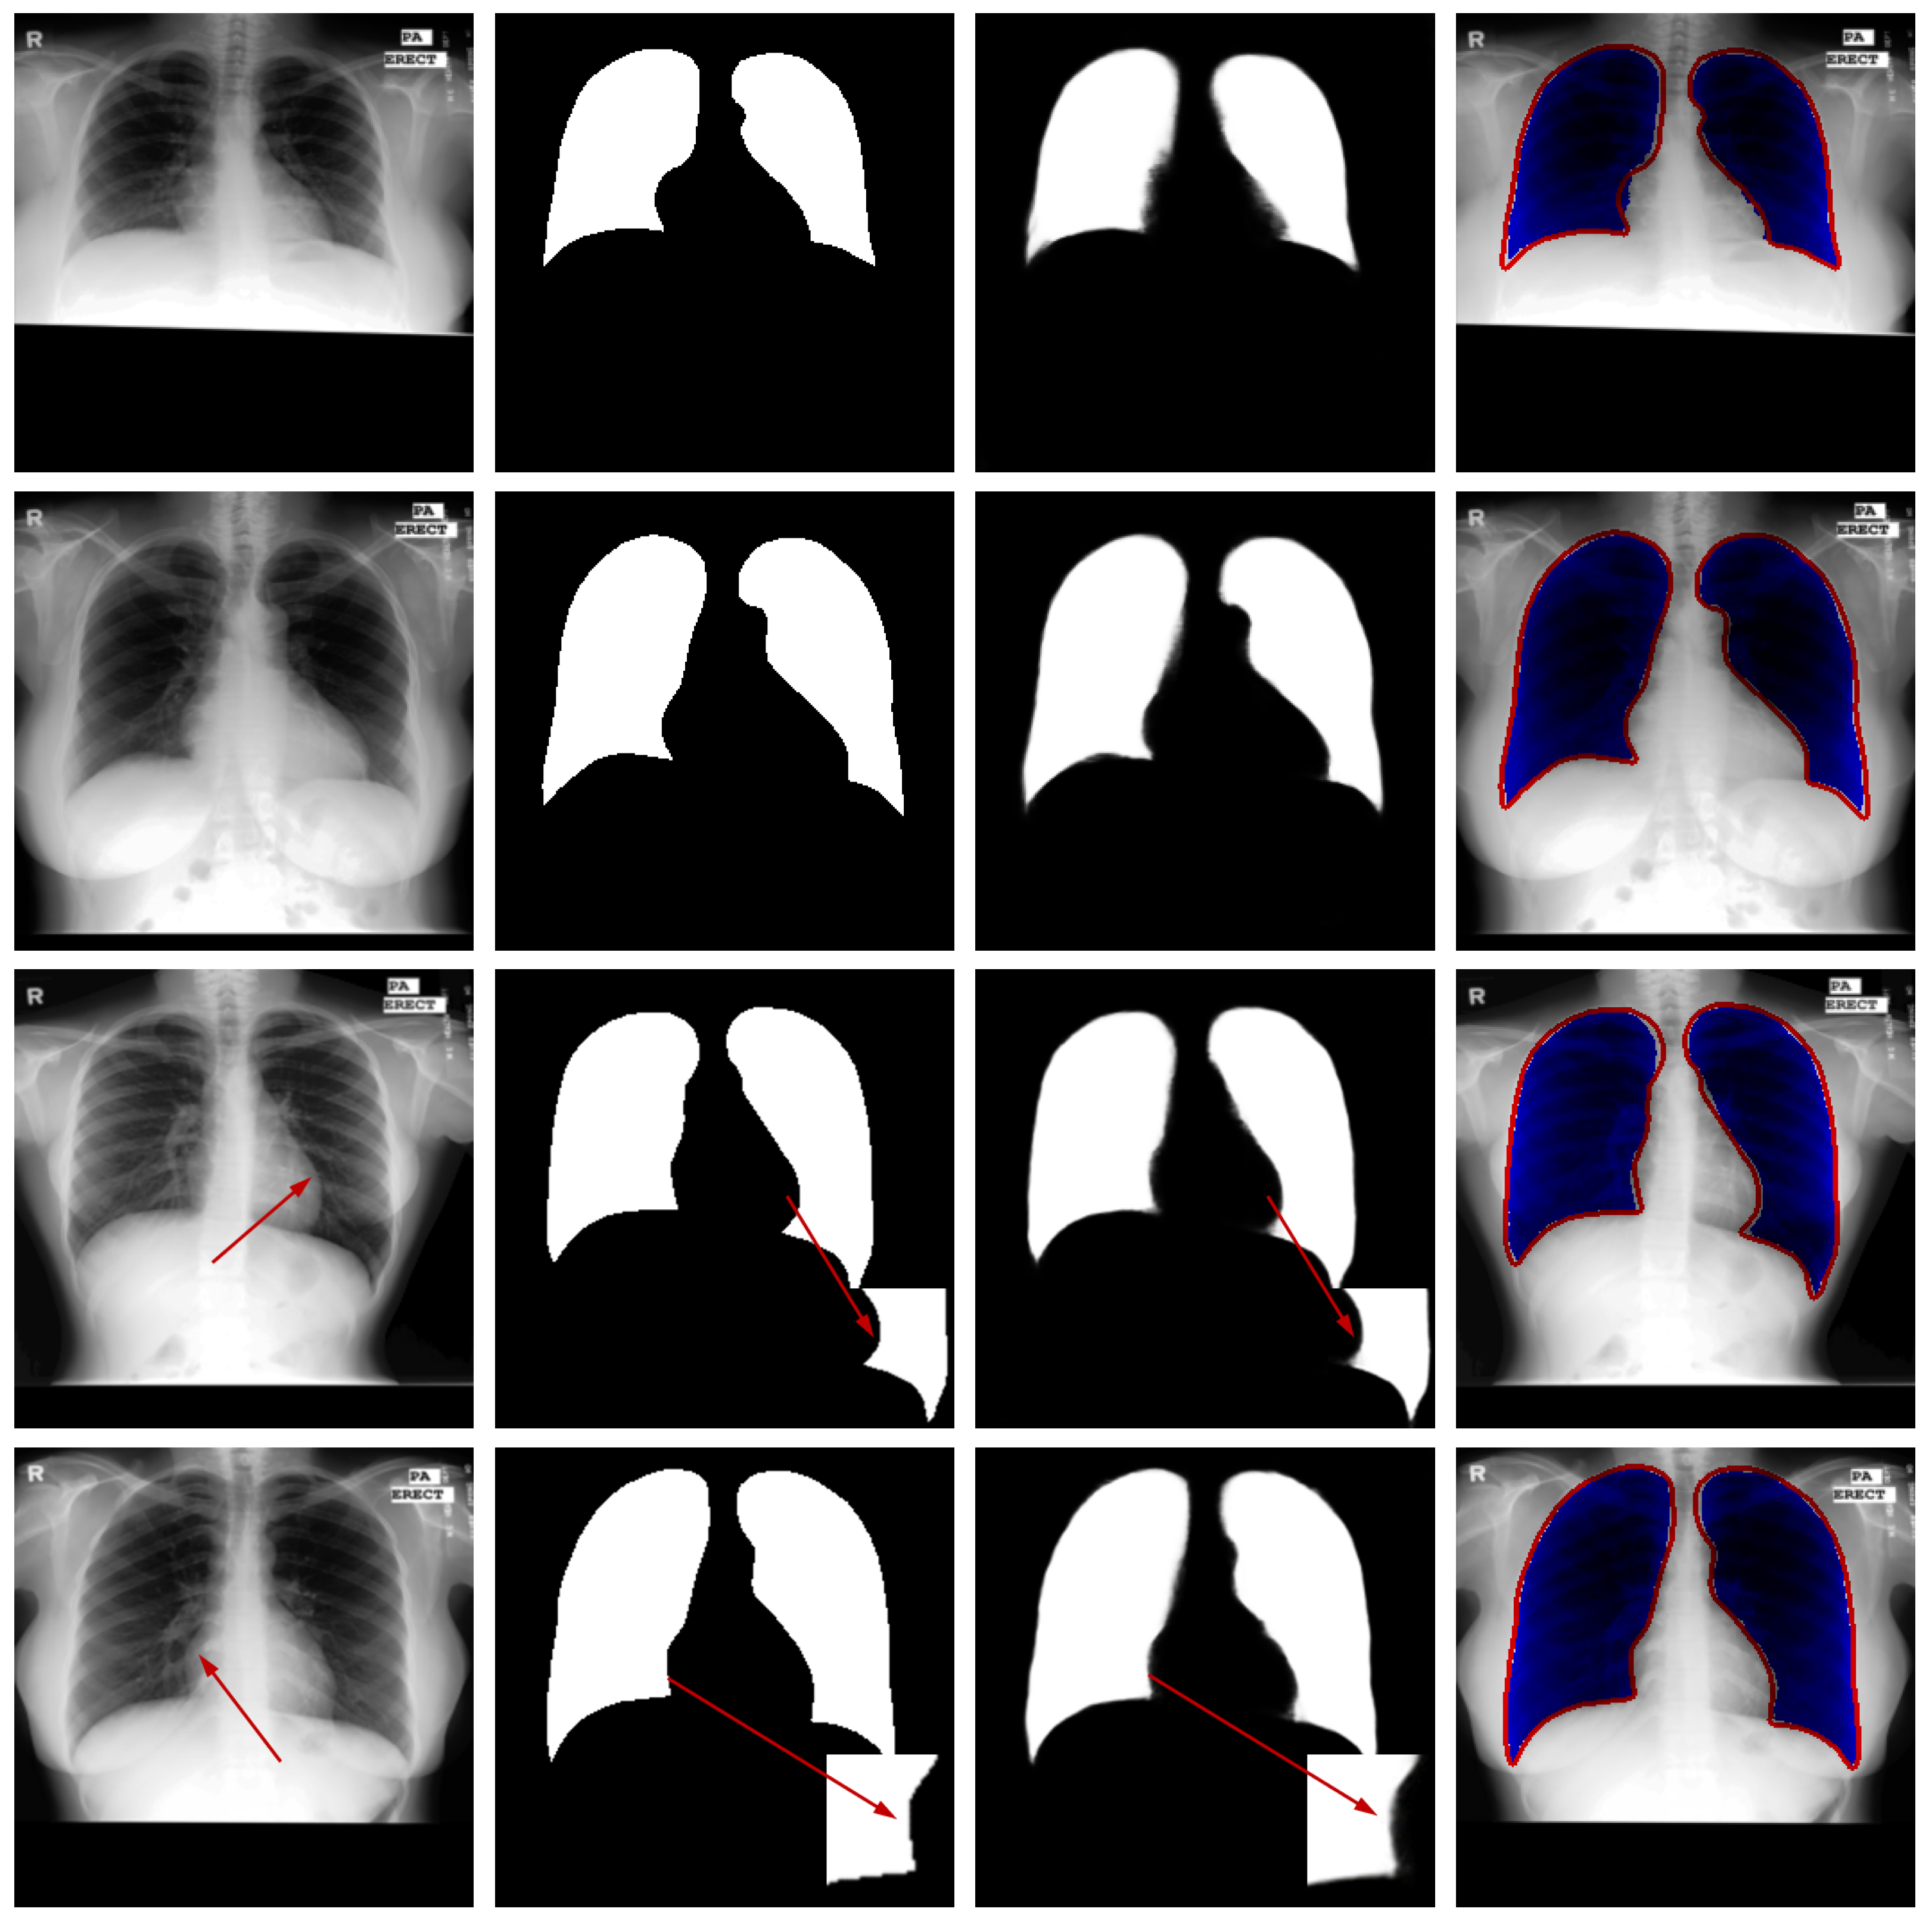

Qualitative Analysis: Figure 6 presents qualitative results from the JSRT dataset to visually assess the segmentation performance. The visualization includes test images, corresponding ground truth, model predictions, and difference maps for comparative analysis.

Figure 6.

Qualitative segmentation results on sample test cases. From left to right: original image from the test dataset, corresponding ground-truth mask, segmentation result generated by the proposed model, and difference map between the ground truth and prediction. The red arrows in the third and fourth rows of the first column in the figure represent difficult recognition areas, the red arrows in the second column represent corresponding ground truth image edge areas, and the red arrows in the third column represent difficult recognition edges in the predicted image. The blue area in the fourth column represents the predicted areas, and the red part represents the ground truth contour.

Visual inspection confirms that the proposed network generates lung masks with well-defined boundaries that closely align with anatomical structures. In most cases, the segmentation results show strong agreement with ground truth annotations, demonstrating the model’s capability to accurately identify pulmonary regions in CT images.

While the overall performance is satisfactory, certain challenging cases reveal limitations in boundary delineation, particularly in regions with low contrast or pathological alterations. These occasional discrepancies highlight opportunities for further refinement and suggest that clinical applications may benefit from optional manual correction in critical scenarios. The visual evidence thus validates the model’s effectiveness while acknowledging areas for future improvement.